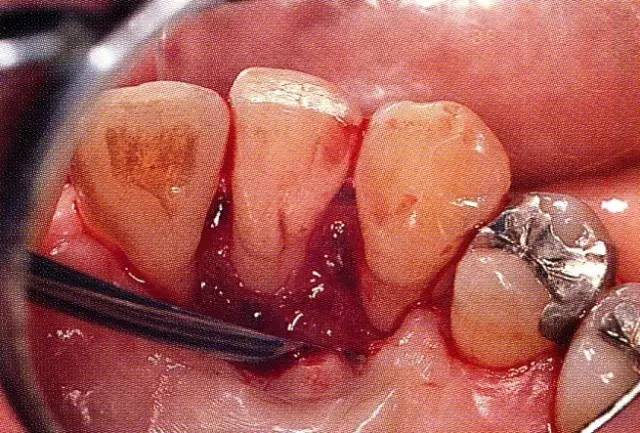

案例3   針對3壁性垂直性骨缺損使用非吸收性膜進行再生治療,再翻瓣時進行骨形態(tài)修整的病例。

▲圖7-1  左下6近中可觀察到3壁性垂直性骨缺損。此病例考慮到齦瓣供血關(guān)系,在前磨牙部位進行了減張切開,沒有進行縱切開。并利用刮治器、牙周外科用車針進行了徹底的骨缺損部位搔刮。